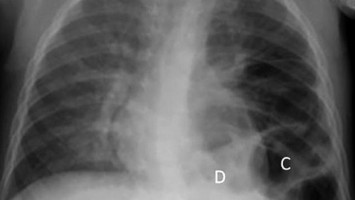

Pulmonale Hypertonie bei angeborener Zwerchfellhernie